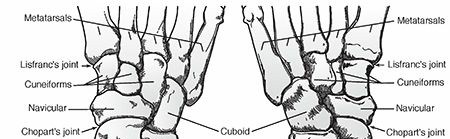

Radiograph demonstrating severe osteomyelitis and bone destruction of the metatarsophalangeal joints, necessitating surgical resection.